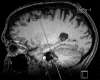

Neurodegenerative diseases are a devastating group of disorders that can be difficult to accurately diagnose. Although these disorders are difficult to manage owing to relatively limited treatment options, an early and correct diagnosis can help with managing symptoms and coping with the later stages of these disease processes. Both anatomic structural imaging and physiologic molecular imaging have evolved to a state in which these neurodegenerative processes can be identified relatively early with high accuracy. To determine the underlying disease, the radiologist should understand the different distributions and pathophysiologic processes involved. High-spatial-resolution MRI allows detection of subtle morphologic changes, as well as potential complications and alternate diagnoses, while molecular imaging allows visualization of altered function or abnormal increased or decreased concentration of disease-specific markers. These methodologies are complementary. Appropriate workup and interpretation of diagnostic studies require an integrated, multimodality, multidisciplinary approach. This article reviews the protocols and findings at MRI and nuclear medicine imaging, including with the use of flurodeoxyglucose, amyloid tracers, and dopaminergic transporter imaging (ioflupane). The pathophysiology of some of the major neurodegenerative processes and their clinical presentations are also reviewed; this information is critical to understand how these imaging modalities work, and it aids in the integration of clinical data to help synthesize a final diagnosis. Radiologists and nuclear medicine physicians aiming to include the evaluation of neurodegenerative diseases in their practice should be aware of and familiar with the multiple imaging modalities available and how using these modalities is essential in the multidisciplinary management of patients with neurodegenerative diseases.©RSNA, 2020.